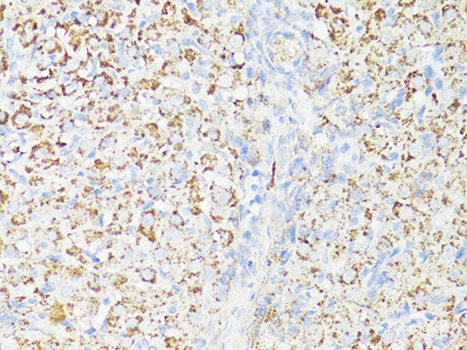

Product information "Anti-MTOR"

The protein encoded by this gene belongs to a family of phosphatidylinositol kinase-related kinases. These kinases mediate cellular responses to stresses such as DNA damage and nutrient deprivation. This protein acts as the target for the cell-cycle arrest and immunosuppressive effects of the FKBP12-rapamycin complex. The ANGPTL7 gene is located in an intron of this gene. Protein function: Serine/threonine protein kinase which is a central regulator of cellular metabolism, growth and survival in response to hormones, growth factors, nutrients, energy and stress signals. MTOR directly or indirectly regulates the phosphorylation of at least 800 proteins. Functions as part of 2 structurally and functionally distinct signaling complexes mTORC1 and mTORC2 (mTOR complex 1 and 2). Activated mTORC1 up-regulates protein synthesis by phosphorylating key regulators of mRNA translation and ribosome synthesis. This includes phosphorylation of EIF4EBP1 and release of its inhibition toward the elongation initiation factor 4E (eiF4E). Moreover, phosphorylates and activates RPS6KB1 and RPS6KB2 that promote protein synthesis by modulating the activity of their downstream targets including ribosomal protein S6, eukaryotic translation initiation factor EIF4B, and the inhibitor of translation initiation PDCD4. Stimulates the pyrimidine biosynthesis pathway, both by acute regulation through RPS6KB1- mediated phosphorylation of the biosynthetic enzyme CAD, and delayed regulation, through transcriptional enhancement of the pentose phosphate pathway which produces 5-phosphoribosyl-1- pyrophosphate (PRPP), an allosteric activator of CAD at a later step in synthesis, this function is dependent on the mTORC1 complex. Regulates ribosome synthesis by activating RNA polymerase III-dependent transcription through phosphorylation and inhibition of MAF1 an RNA polymerase III-repressor. In parallel to protein synthesis, also regulates lipid synthesis through SREBF1/SREBP1 and LPIN1. To maintain energy homeostasis mTORC1 may also regulate mitochondrial biogenesis through regulation of PPARGC1A. mTORC1 also negatively regulates autophagy through phosphorylation of ULK1. Under nutrient sufficiency, phosphorylates ULK1 at 'Ser- 758', disrupting the interaction with AMPK and preventing activation of ULK1. Also prevents autophagy through phosphorylation of the autophagy inhibitor DAP. mTORC1 exerts a feedback control on upstream growth factor signaling that includes phosphorylation and activation of GRB10 a INSR-dependent signaling suppressor. Among other potential targets mTORC1 may phosphorylate CLIP1 and regulate microtubules. As part of the mTORC2 complex MTOR may regulate other cellular processes including survival and organization of the cytoskeleton. Plays a critical role in the phosphorylation at 'Ser-473' of AKT1, a pro-survival effector of phosphoinositide 3-kinase, facilitating its activation by PDK1. mTORC2 may regulate the actin cytoskeleton, through phosphorylation of PRKCA, PXN and activation of the Rho-type guanine nucleotide exchange factors RHOA and RAC1A or RAC1B. mTORC2 also regulates the phosphorylation of SGK1 at 'Ser-422' (PubMed:12087098, PubMed:12150925, PubMed:12150926, PubMed:12231510, PubMed:12718876, PubMed:14651849, PubMed:15268862, PubMed:15467718, PubMed:15545625, PubMed:15718470, PubMed:18497260, PubMed:18762023, PubMed:18925875, PubMed:20516213, PubMed:20537536, PubMed:21659604, PubMed:23429703, PubMed:23429704, PubMed:25799227, PubMed:26018084). Regulates osteoclastogenesis by adjusting the expression of CEBPB isoforms. [The UniProt Consortium]

| Application: | WB, IHC, IF |